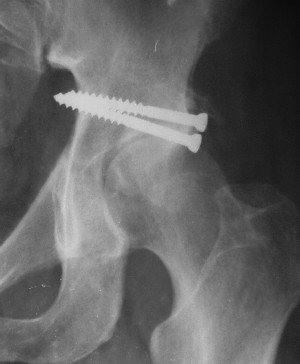

Послеоперационный снимок прямой 5/05/03

Послеоперационный снимок боковой 5/06/03

Больной 18 мая 2003 года в автоаварии получил перелом левой вертлужной впадины, вывих бедра. Госпитализирован в один из стационаров области.Вывих вправлен. В последствии бедро вывихивалось еще дважды. На консультацию был представлен снимок от 19.05.03г., больной переведен к нам 3.06.03г. Снимок при поступлении - перелом впадины, задне-верхний вывих бедра. 05.06.2003 г. выполнено открытое вправление вывиха левого бедра и остеосинтез стенки вертлужной впадины двумя винтами. Послеоперационный период без осложнений. Объем движений в левом тазобедренном суставе восстановился полностью. Выписан на амбулаторное лечение в удовлетворительном состоянии с рекомендациями 3 месяца ходить на костылях без нагрузки на оперированную конечность. На контрольных рентгенограммах левого тазобедренного сустава 13.10.2003 г. - признаки консолидации перелома; плотность, форма головки и состояние суставных поверхностей удовлетворительные. Разрешена дозированная осевая нагрузка, на конечность с использованием дополнительной опоры. 19.12.2003 г. больной обратился с жалобами на боли в левом тазобедренном суставе. На рентгенограммах левого тазобедренного сустава 19.12.2003 г., 20.02.04г. - асептичекий некроз головки бедра. 5.04.04г. - эндопротез. Сейчас ходит без трости, не хромает. Особенность эндопротезирования - при удалении винтов прослежена линия перелома заднего края впадины и предложено установить чашку несколько меньшего диаметра, чтобы она была покрыта несломанной частью.